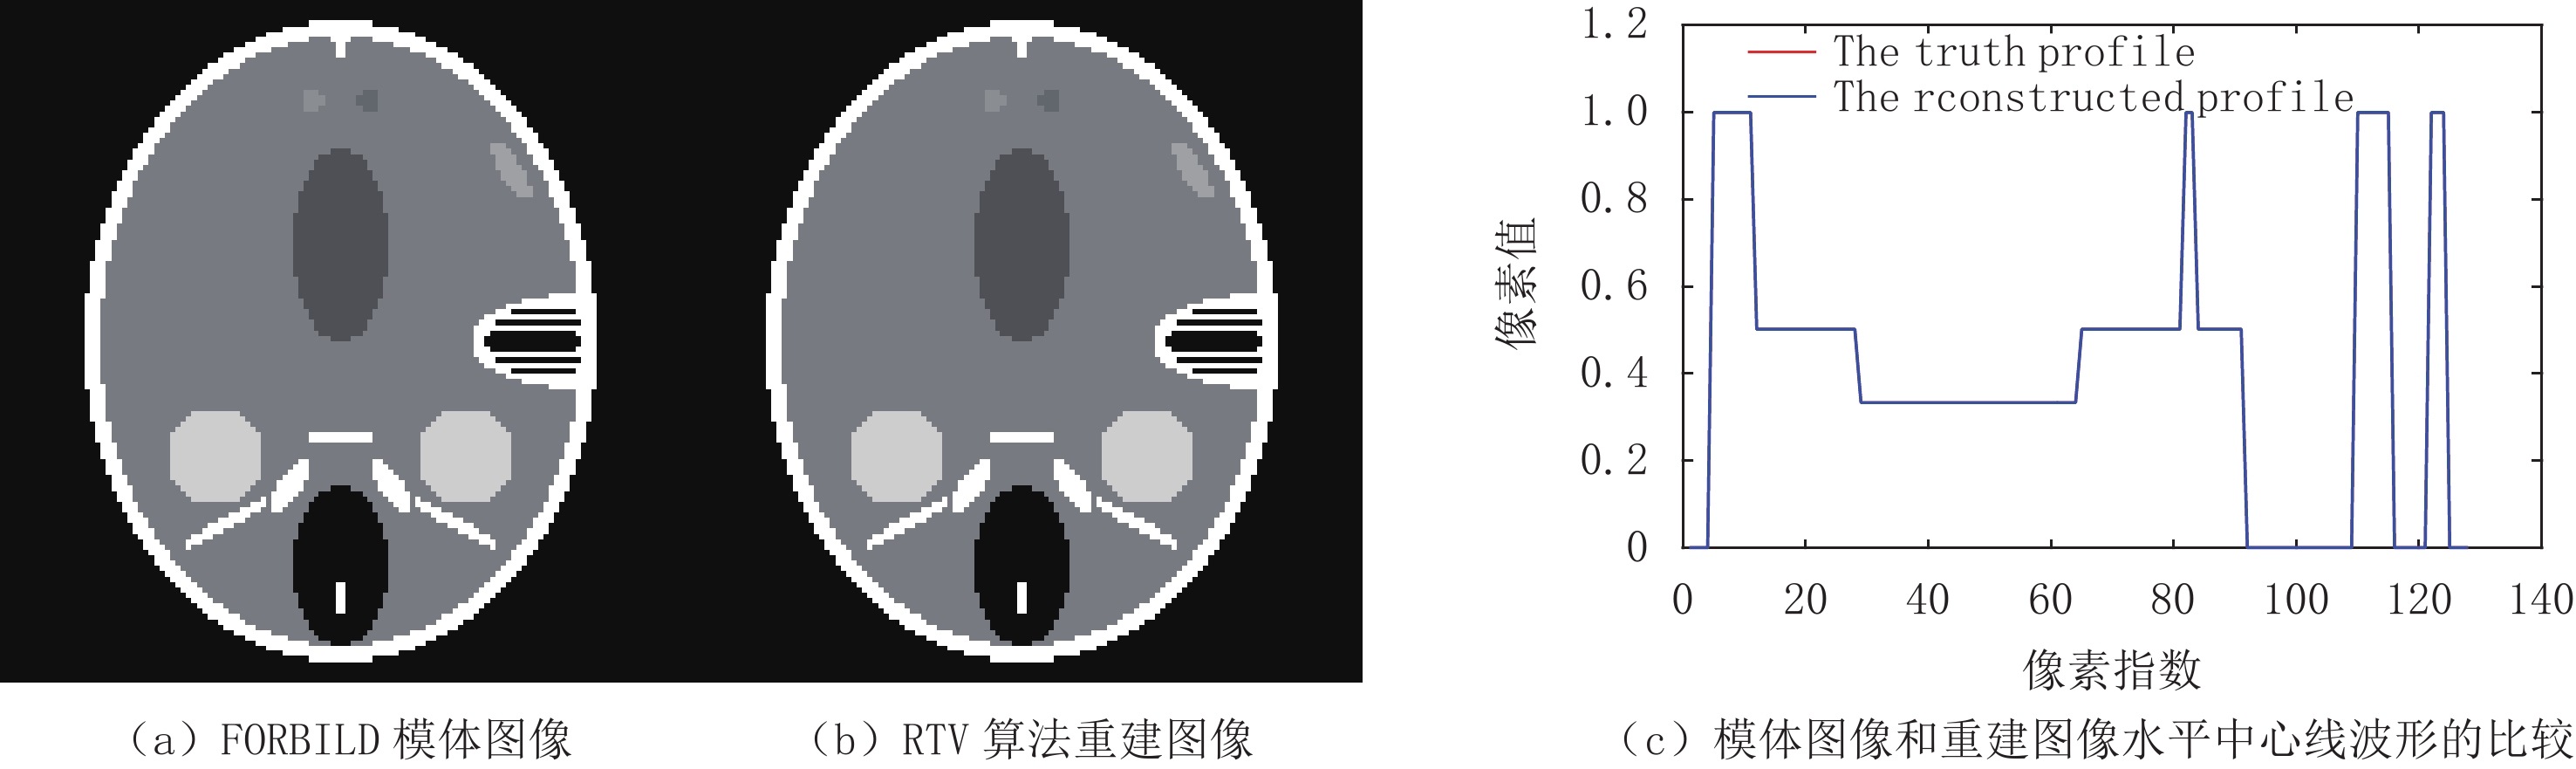

对于算法收敛性的评估,引入以下3个度量标准,通过观察这3个度量标准来判断算法的收敛性:

$$ {{{{M}}_1}\left( n \right) = {\rm{RMSE}}\Big( {{{\boldsymbol{f}}_n},{{\boldsymbol{f}}_{{\rm{truth}}}}} \Big)} \text{,} $$ (18) $$ {{M_2}\left( n \right) = \big\| {{\boldsymbol{g}} - {\boldsymbol{A}}{{\boldsymbol{f}}_n}} \big\|} _2\text{,} $$ (19) $$ {{M_3}\left( n \right) = \frac{{{{\big\| {{{\boldsymbol{f}}_n}} \big\|}_{{\rm{TV}}}} - {{\big\| {{{\boldsymbol{f}}_{{\rm{truth}}}}} \big\|}_{\rm{TV}}}}}{{{{\big\| {{{\boldsymbol{f}}_{{\rm{truth}}}}} \big\|}_{{\rm{TV}}}}}}} \text{,} $$ (20) 其中(18)式代表重建图像与真实图像间的均方根误差;(19)式代表重建图像的投影与真实投影间的差异,(20)式代表重建图像的TV值与真实图像TV值之间的相对误差。

在此实验的研究中,投影数据是充分且准确的,所以在重建图像达到收敛时,这些度量标准要达到充分小,表示该算法在高精度重建的同时达到了收敛。如图4和图5所示,其分别展示了在重建Shepp-Logan和FORBILD模体时RTV最小化重建算法的收敛行为,其中图(a)~图(c)图分别展示了(18)~(20)式所示的度量标准的迭代走势。

图4和图5中的(a)图显示的是图像误差的迭代走势。而在重建这两个模体时,其

${M_1}\left( n \right)$ 分别迭代到200多次和300多次时达到了10-4,在迭代到500次时分别达到了10-5和10-7,如果继续迭代,其${M_1}\left( n \right)$ 还会有继续下降的趋势;(b)图显示了数据误差的迭代走势,从图中可以看出数据误差在不断减小,但是在重建过程中有一个向上的抖动,这种现象是TV类算法在迭代过程的一个特点,在迭代过程中经常出现,并不会影响该算法的收敛性,振动之后,其相对误差会继续减小,这说明优化模型的解仍然趋向收敛;(c)图显示了TV值的相对误差,从图中可见其整体下降趋势,并且在迭代到500次之后都还有继续下降的趋势。总之,无论是从(a)图,还是(b)图、(c)图来看,重建结果都已在有限次的迭代次数下使误差达到了充分小,并且还有继续下降的趋势,直至达到其收敛态。